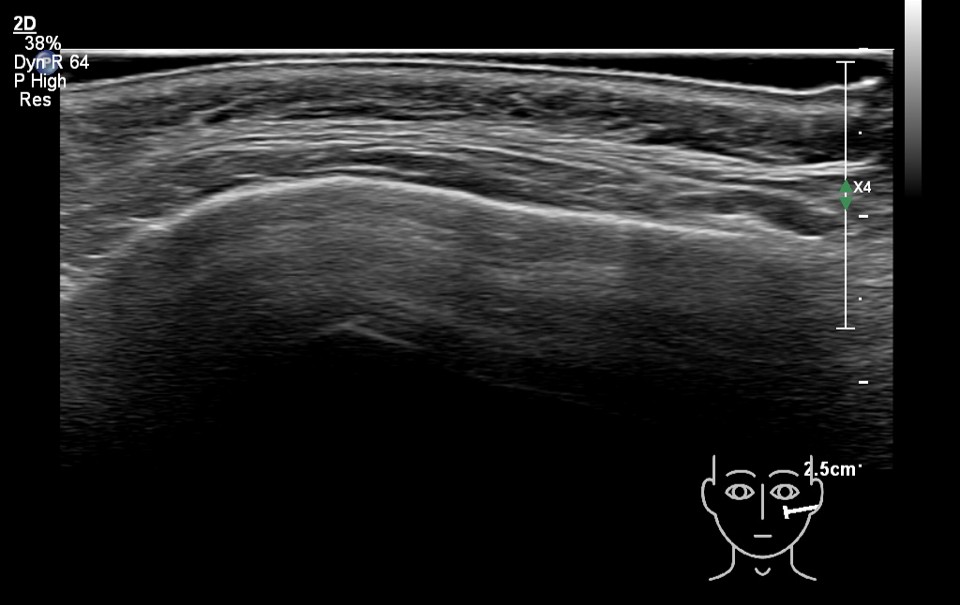

Study the first image to recognize the different layers. If you are sure about the layers, swipe to the second image to view the answer (if applicable).